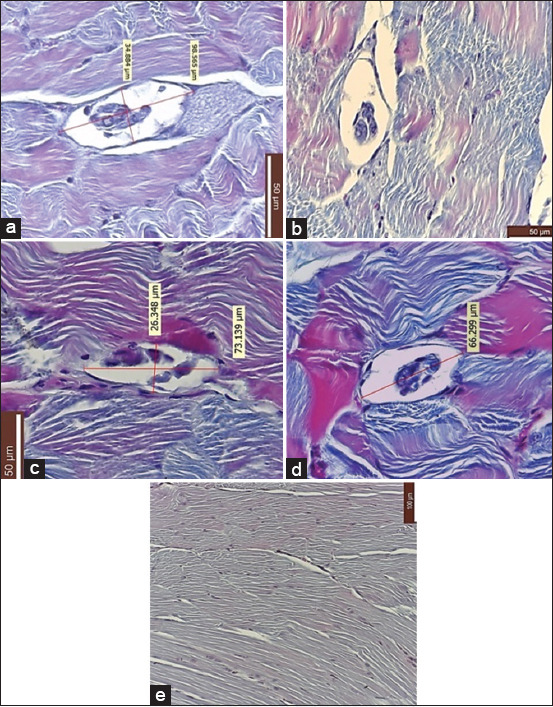

Materials and methods: Muscle samples (50 g each) from a wild boar naturally infected with T. britovi were frozen for 56 days at four temperatures: -18°C, -20°C, -29°C, and -40°C. Post-thaw, larval viability was assessed through artificial digestion, and infectivity was tested in a murine model using BALB/c mice. Each experimental group (n = 5 mice) received 120 larvae through gavage over 2 days. After 56 days, mice were euthanized, and muscle tissues were examined histologically. Molecular confirmation was performed using multiplex polymerase chain reaction on formalin-fixed tissues.

Results: Despite larval motility post-thaw, no viable T. britovi DNA was detected in the muscle tissues of infected mice. Histological examination showed structures resembling Trichinella cysts in all experimental groups, but these were not molecularly confirmed. The control group remained negative throughout.